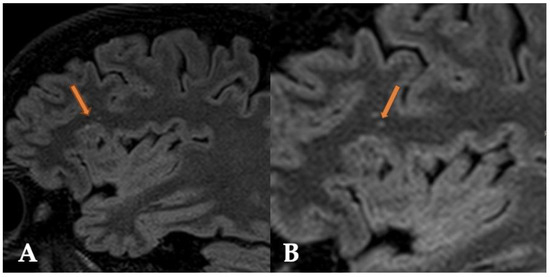

2.2. Case 2